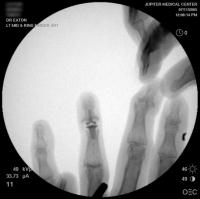

Intraoperative fluoroscopy.

Intraoperative fluoroscopy using the same technique as above. The trial spacers: